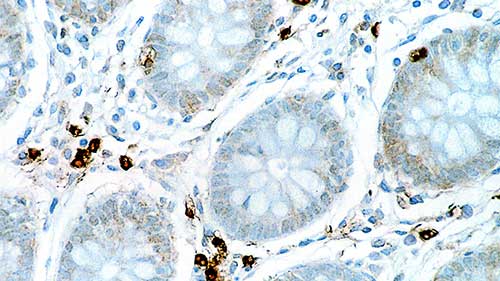

IHC-P analysis of human colon tissue using GTX01893 IL6 antibody [10C12]. Note cytoplasmic staining of a proportion of lymphoid cells.